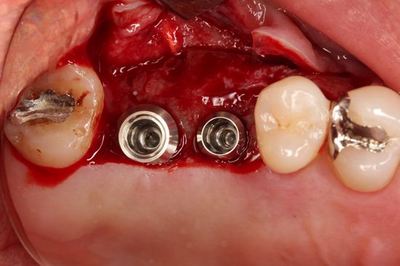

無事埋入を終えました。

![]()

挿入ジグを外しました。インプラントネックが見えています。